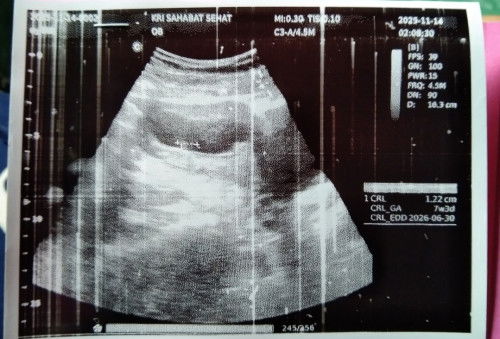

Crl ukuran janin GA usia janin . D bawahnya tuh perkiraan lahir

CRL = panjang janin GA = usia kandungan EDD = HPL

CRL itu setau saya panjang janin skitar 3.6cm.